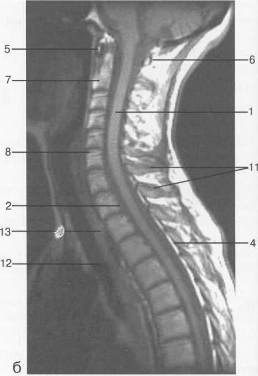

Рис. 12. МРТ. Срединное

сагиттальное изображение шейного отдела позвоночника. а-Т2-ВИ;б-Т1-ВИ.

- спинной мозг; 2 -

субарахноидальное пространство; 3 - дуральный мешок (задняя стенка); 4 -

эпидуральное пространство; 5 - передняя дуга С1; 6 - задняя дуга С1; 7 - тело

С2; 8 - межпозвонковый диск; 9 - гиалиновая пластинка; 10 - артефакт

изображения; 11 - остистые отростки позвонков; 12 - трахея; 13 - пищевод.

Рис. 13. МРТ. Парасагиттальное

изображение шейного отдела позвоночника. а-Т2-ВИ;б-Т1-ВИ.

- боковая масса С,; 2 - задняя

дуга С,; 3 - тело Сп; 4 - дуга Сш; 5 - позвоночная артерия на уровне сегмента V2;

6 - спинномозговой нерв; 7 - эпидуральная жировая клетчатка; 8 - тело Th,;

9 - ножка дуги Thn;

10 - аорта; 11 - подключичная артерия.